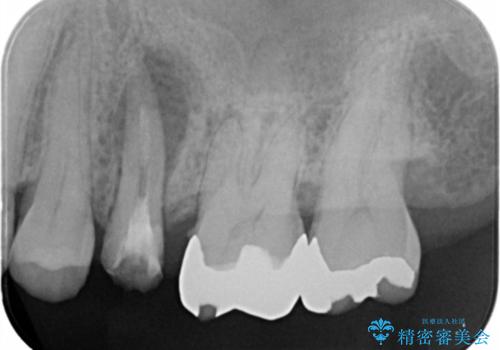

歯茎が腫れる インプラントでの治療

- 40代女性

- 10ヶ月

- 5-10回

- 左上5/インプラント:242,000円 骨増生:55,000円 カスタムアバットメント:110,000円 インプラント用仮歯:22,000円 ジルコニアクラウン:121,000円 合計550,000円費用は治療当時の料金となります